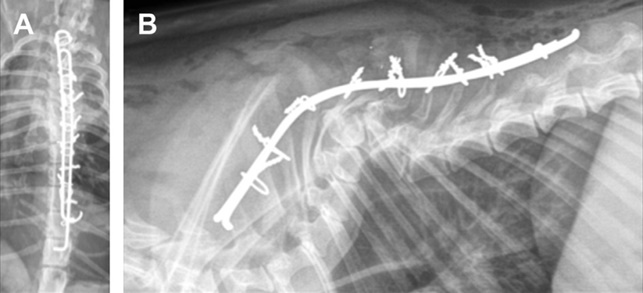

Κοιλιοραχιαίο και πλάγιο ακτινογράφημα που δείχνει τη σπονδυλοδεσία στη θωρακική μοίρα της ΣΣ σε σκύλο με ημισπόνδυλο.

Ήλοι με θετικό σπείρωμα έχουν εισαχθεί στον Θ6, Θ7 και Θ8 και έχουν συνδεθεί μεταξύ τους με PMMA σε σκύλο με ημισπόνδυλο.